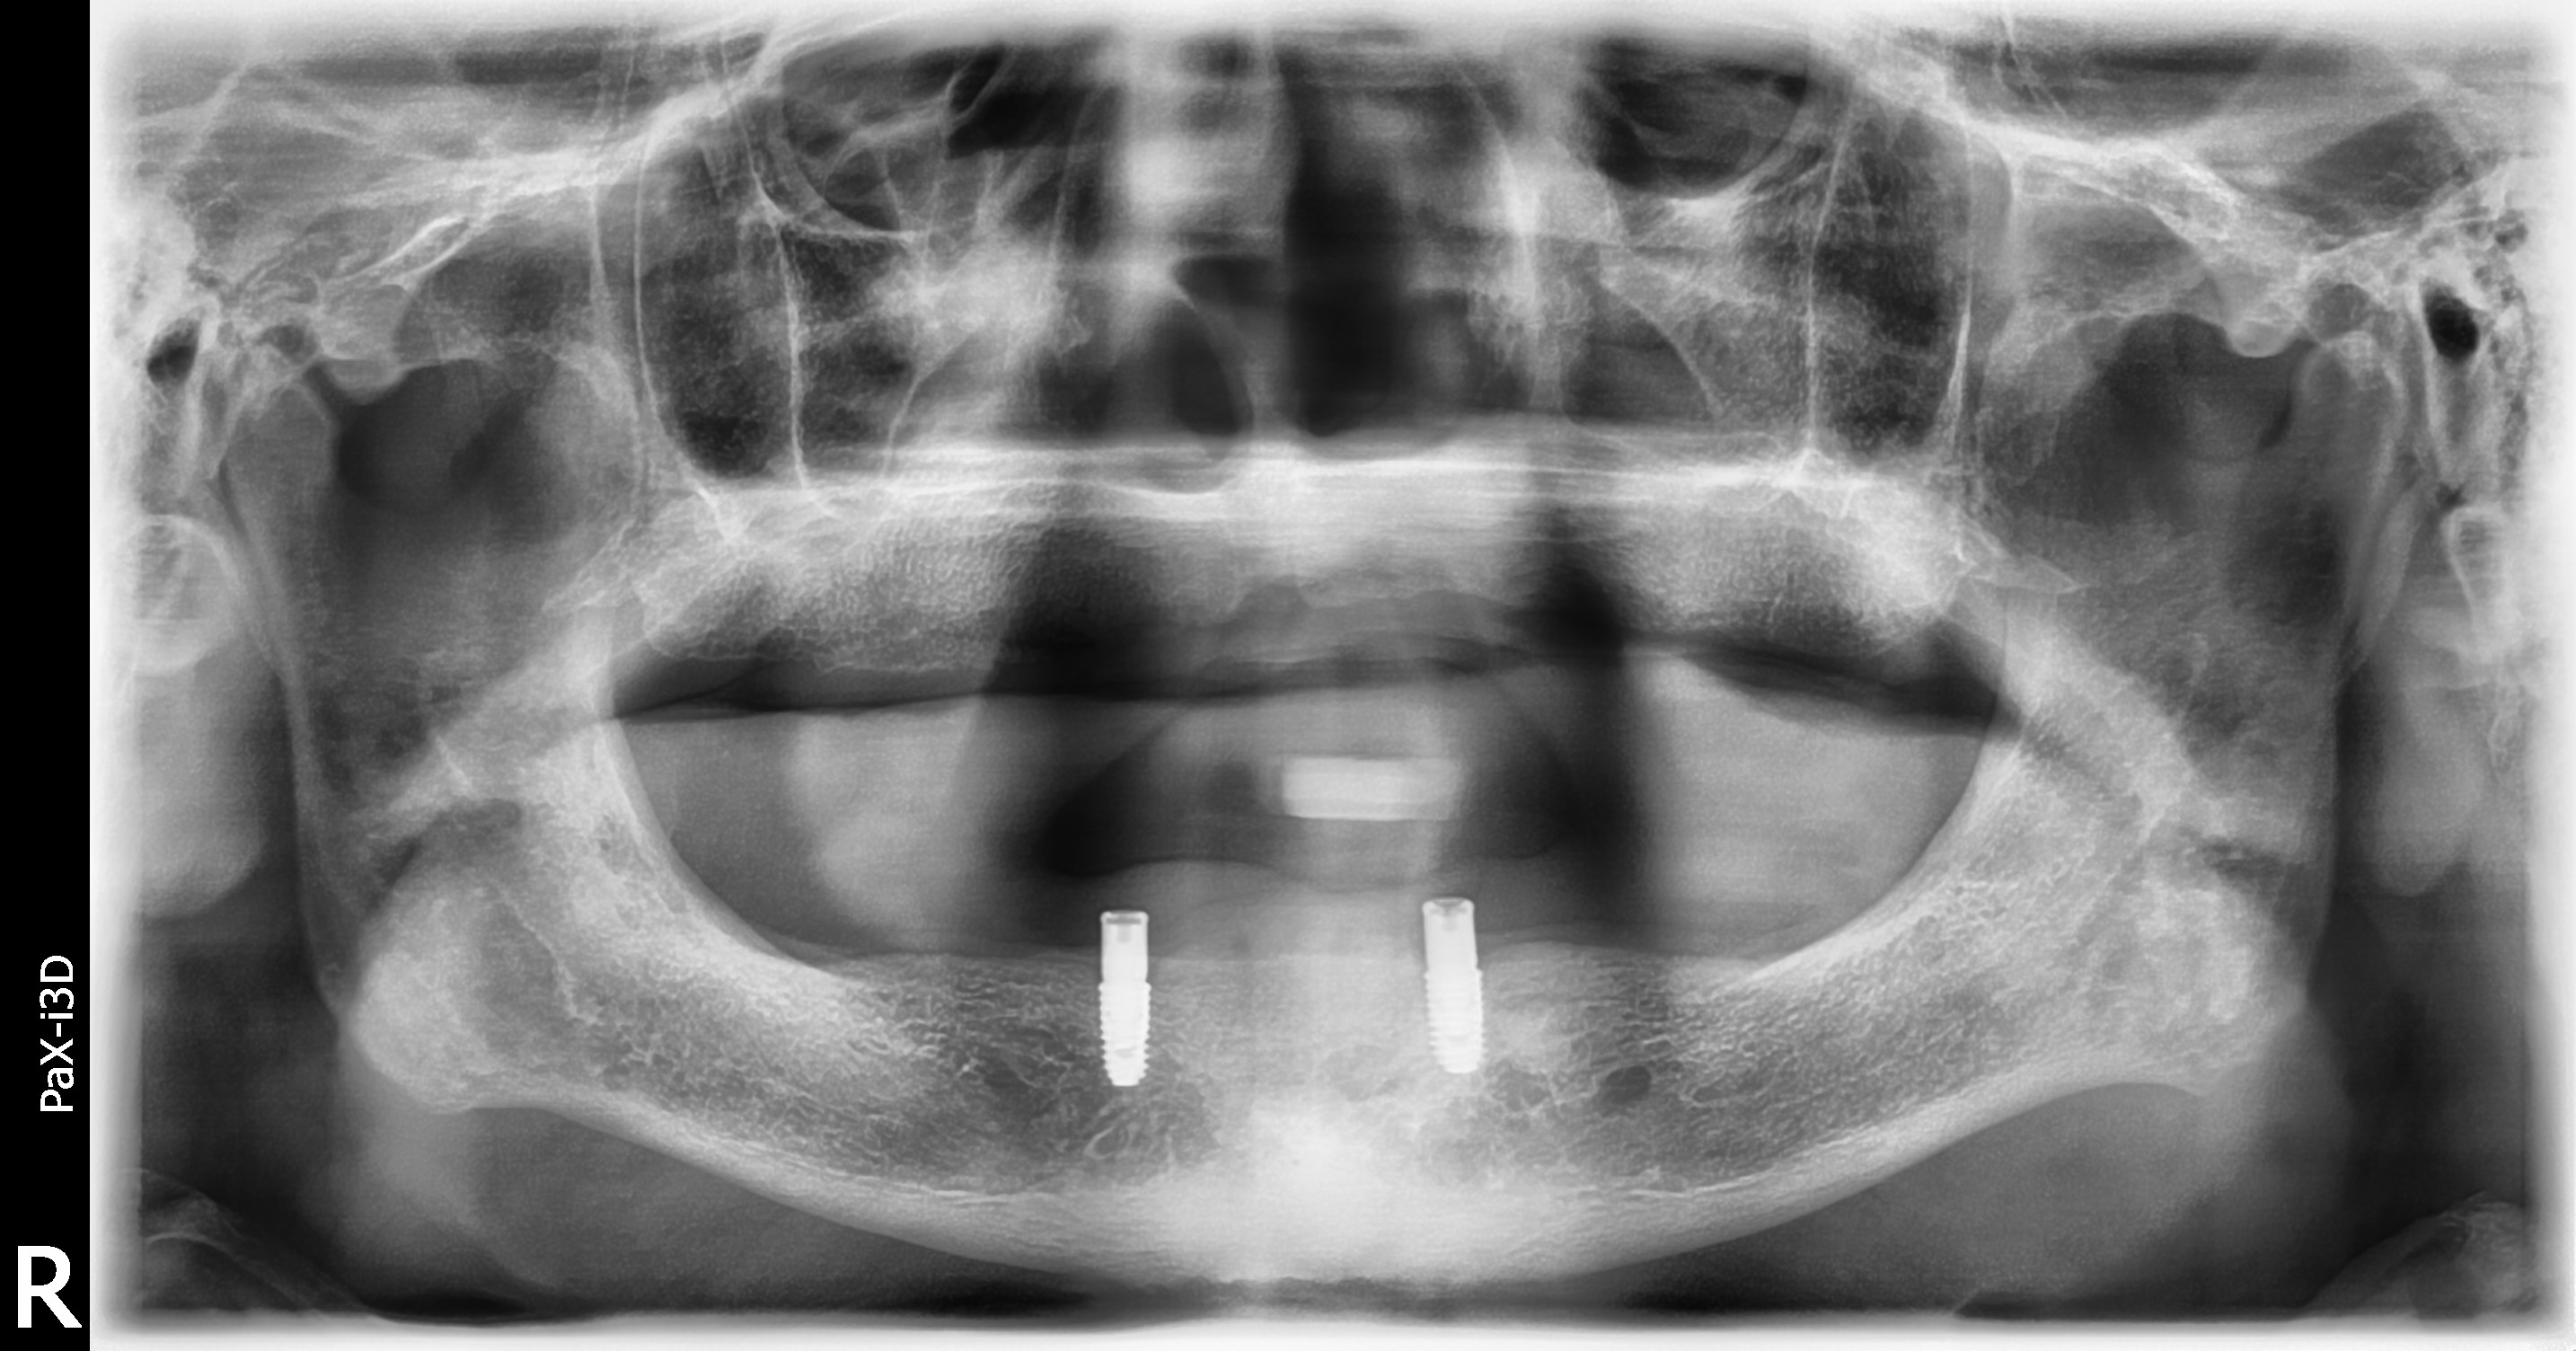

임플란트 틀니